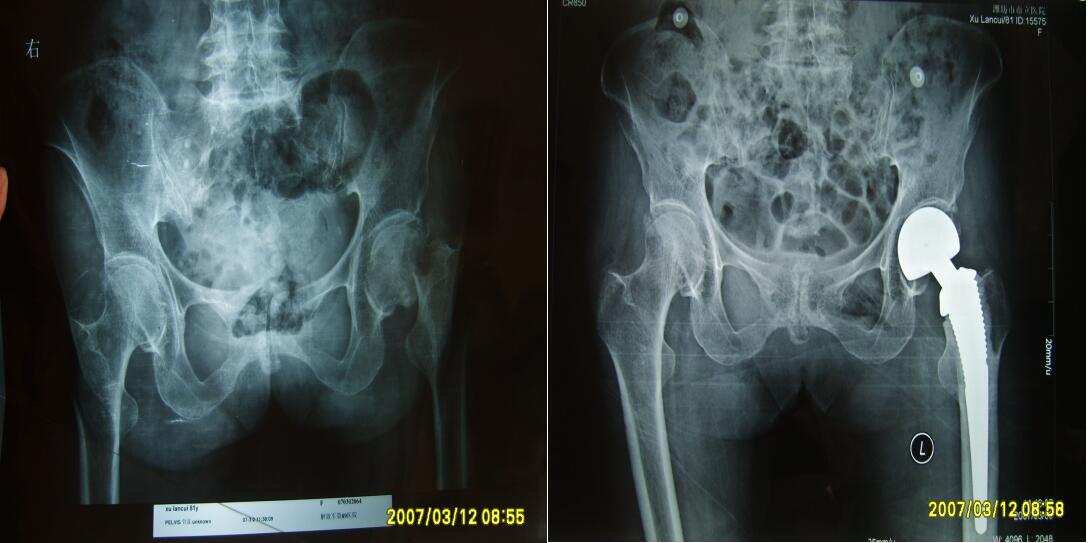

更多成功手術(shù)案例展示:

部分髖關(guān)節(jié)置換